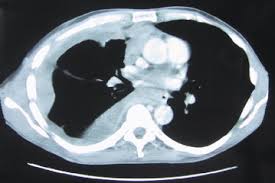

Diffuse Malignant Mesothelioma Lung Cancer - Diagnostic Imaging And Workup Of Malignant Pleural Mesothelioma / Glioblastoma is an aggressive cancer of the brain.

Diffuse Malignant Mesothelioma Lung Cancer - Diagnostic Imaging And Workup Of Malignant Pleural Mesothelioma / Glioblastoma is an aggressive cancer of the brain.. Here we look at some of the key symptoms of this disease to watch out for. When it comes to monitoring your health, your heart and lungs are right at the top of the list of important organs you should focus on. Lung cancer is a serious illness which none of us wish to face. Learn the symptoms, prognosis and treatment options for malignant mesothelioma. Abnormal cells grow and can form tumors.